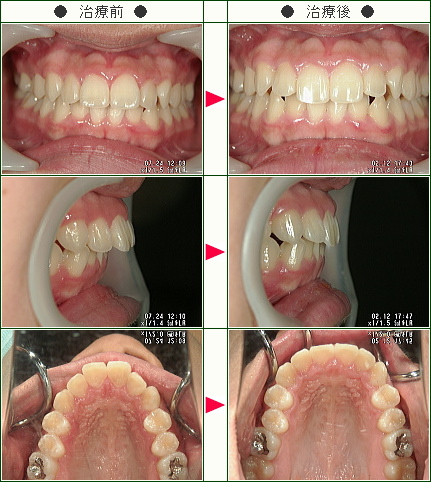

☆出っ歯矯正症例(佐野様 14歳 女性)

▼患者様の感想

マウスピースをつける時、当たり前だが、痛かった。

先生やスタッフさんの印象や対応が本当にとても感じよく、安心して治療に臨めた。

とても丁寧な説明をしてくれたので、わかりやすかったです。

設備が整っていて、一つ一つがきれいで気持ちが良かった。